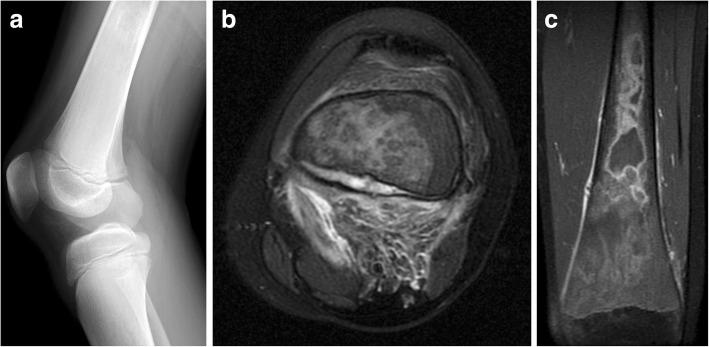

戈谢病是一种遗传性代谢紊乱疾病,会导致溶酶体酶β-葡萄糖脑苷脂酶缺乏,进而引起多个器官内异常巨噬细胞(“戈谢细胞”)的蓄积,最明显的是影响肝脏、脾脏和骨髓。作为最常见的糖脂代谢紊乱疾病,对于接触这些患者的放射科医生而言,熟悉器官和骨髓受累的影像学进展并了解影像学在临床决策中的作用非常重要。近期出现了可用于测量脂肪分数的商用、可靠且可重复的定量MRI采集方法,这促使人们重新审视骨髓受累定量评估的作用。本文综述了戈谢病的各种影像学表现,并讨论了用于确定实体器官和骨髓受累情况的更优化定量方法,重点是包括弹性成像在内的其他定量方法的未来应用。